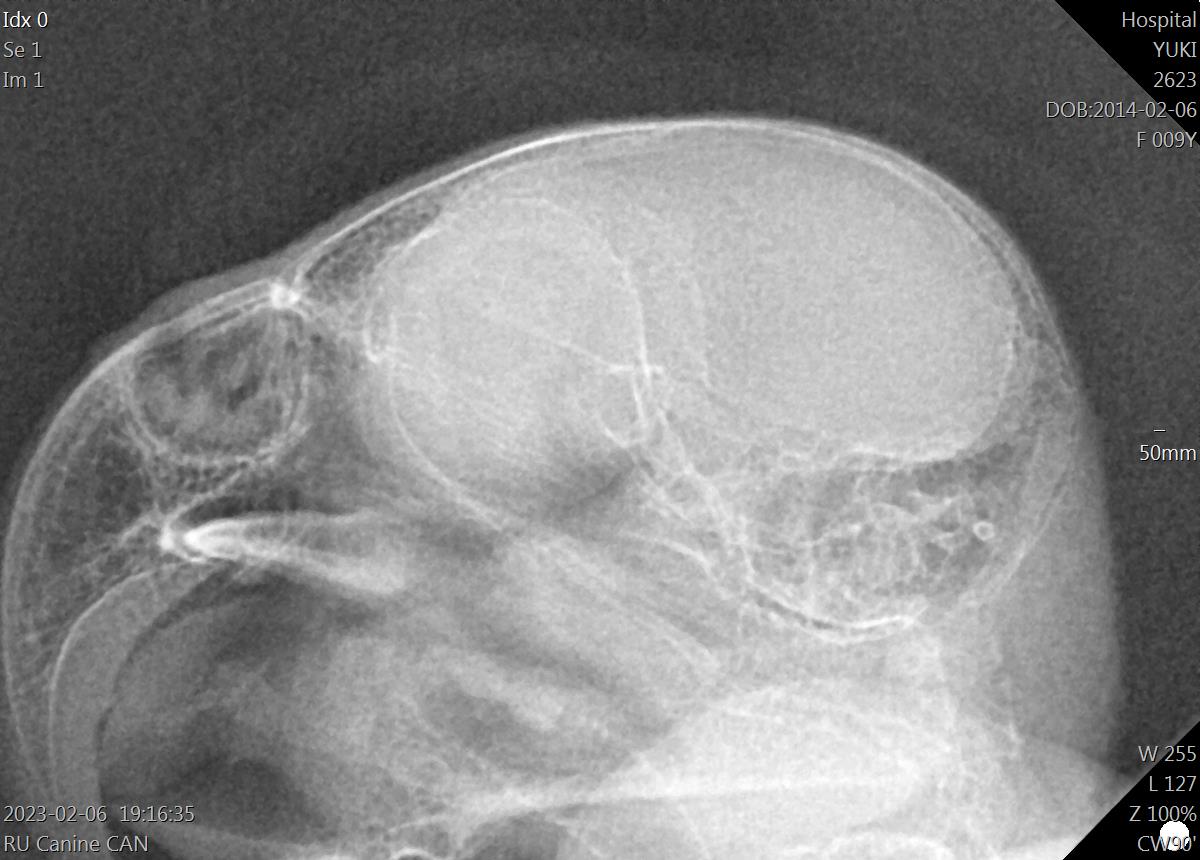

En nuestro centro veterinario contamos con una máquina de Radiología digital directa, con la que conseguimos radiografías de elevada calidad, permitiéndonos además reducir al mínimo la dosis de Rayos X gracias a la gran eficiencia de este método.

Con la radiología digital directa conseguimos obtener la imagen radiográfica en pocos segundos en la pantalla digital, sin laboriosos trabajos de procesado de la radiografía, así de simple y fácil. Además esto nos permite poder procesar las radiografías que el animal requiera sin tener que mantenerlo inmovilizado más que unos segundos.

En nuestro centro hemos invertido en un buen aparato de radiología porque nos importa la calidad y el detalle, en especial cuando tratamos a mascotas de muy reducido tamaño, o necesitamos visualizar aspectos o detalles muy concretos.